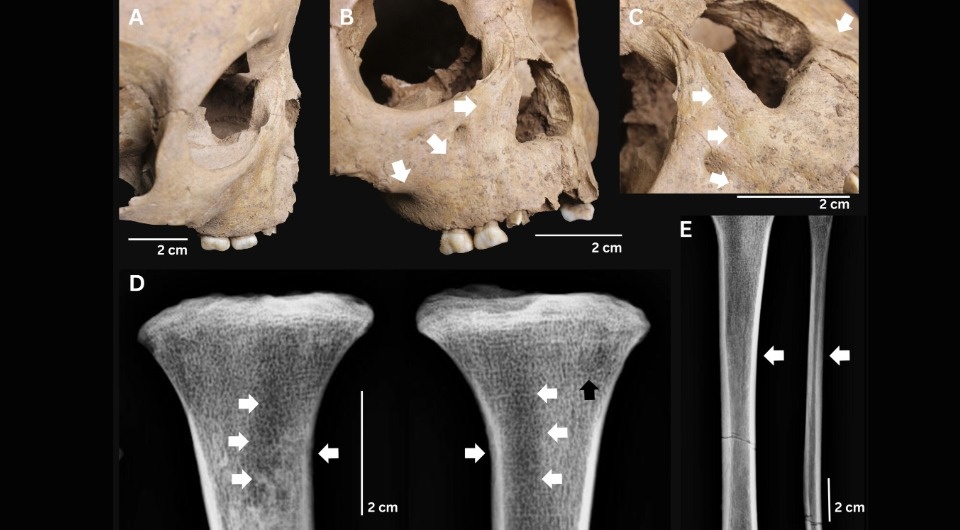

Melandri Vlok et al. / International Journal of Osteoarchaeology, 2026

В результате проведенного анализа ученых заинтересовали останки трех человек, причем все они были детьми. Два из них происходили из археологического памятника Ман-Бак, который расположен на севере Вьетнама и относится к эпохе неолита (около 4–3,5 тысячи лет назад). Первые останки представляли собой хорошо сохранившийся скелет ребенка, который прожил примерно 18 месяцев. На его правой плечевой и левой большеберцовой костях, а также на правой ключице исследователи выявили похожие на гуммы образования, что обычно свойственно для третичного сифилиса. Кроме того, на лобной кости ученые заметили признаки симптома Парро. Похожие на проявления сифилиса аномалии присутствовали и на зубах ребенка, поэтому ученые заключили, что он, по-видимому, страдал от врожденного трепонематоза.

Второй ребенок из памятника Ман-Бак был постарше — он прожил около пяти лет. На его хорошо сохранившемся скелете сначала по фотографиям, а затем и при непосредственном обследовании ученые также выявили признаки аналогичного заболевания: седловидная деформация носа, разрастание костной ткани на отростках верхней челюсти, кортикальное разрастание (гиперостоз) на большеберцовой и малоберцовой кости. Помимо этих потенциальных признаков врожденного трепонематоза, палеопатологи также диагностировали у малыша проявления цинги.